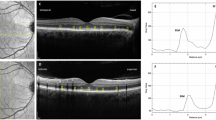

Figure 1 shows the OCTA features in NPDR group.

Example of images from one of our patients. (A) Multifocal electroretinogram (mfERG) bioelectrical responses in one representative eye affected by non-proliferative diabetic retinopathy (NPDR). The 61 hexagons trace arrays, subtending 15° of visual field, were sub-grouped in concentric annular areas (rings, R). We measured the N1-P1 response amplitude density (RAD) of mfERG responses recorded from three isolated and combined averaged rings with increasing eccentricity from the fovea: 0 to 2.5 (R1), 2.5 to 5 (R2), 5 to 10 (R3), 0 to 5 (R1 + R2), 0 to 15 (R1 + R2 + R3) degrees. (B) Choriocapillaris optical coherence tomography angiography (OCTA) slab acquired with PLEX Elite device. Several small regions of signal voids (dark spots scattered throughout the image) are evident on the enface OCTA image of the choriocapillaris and represent regions of decreased perfusion. (C) Ellipsoid zone (EZ) OCTA slab acquired with PLEX Elite device. The structural image at the level of the EZ shows regions of reduced reflectivity, which constitutes a surrogate for photoreceptor damage. (D) Corresponding structural optical coherence tomography acquired with PLEX Elite device.

To do so, we employed OCT/OCTA analysis and mfERG recordings. Overall, we found a negative correlation between EZ “normalized” reflectivity and CC features (FD%) in T1D eyes without DR. More importantly, we showed a significant relationship between abnormal outer retina functional responses and CC features (CC FDa and CC FD%) in NPDR T1D eyes (Fig. 1). For the best of our research, we excluded patients affected with macular edema.